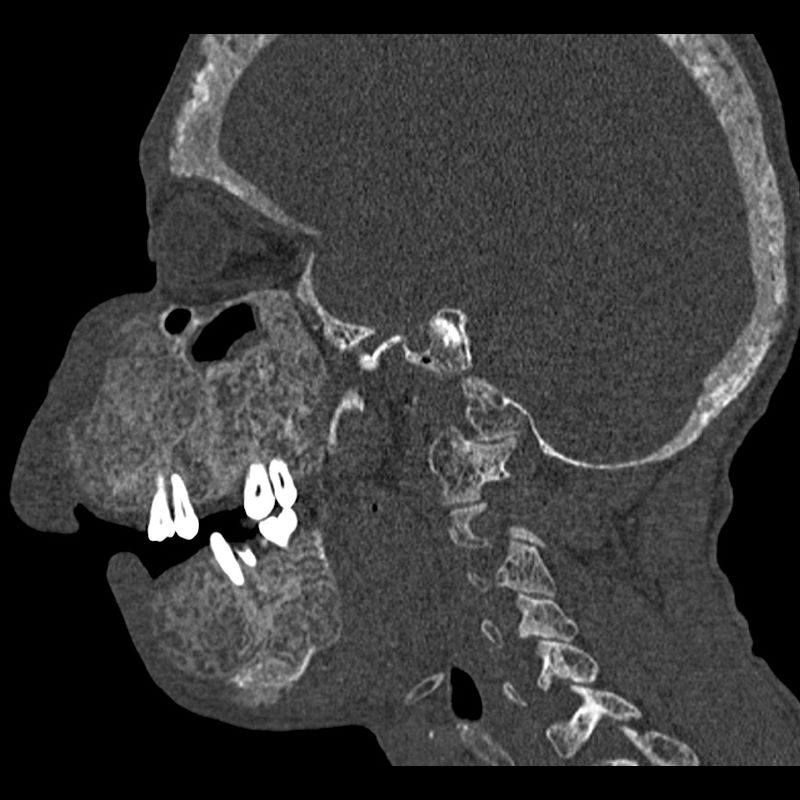

29 yaş, Erkek

Yüzde belirgin şişlik

Fibröz displazi

Kraniofasiyal fibröz displazi

FİBRÖZ DİSPLAZİ